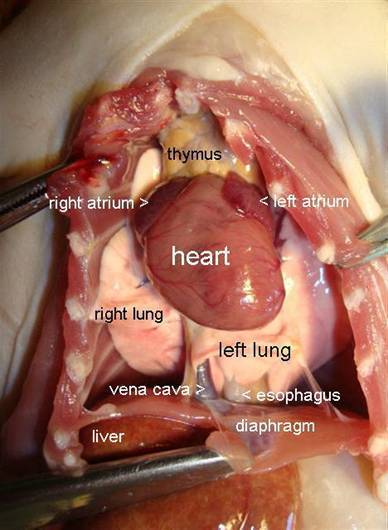

In

this picture, the front of the chest with the ribs has been removed for a

better view. This heart is fairly normal looking, although somewhat larger than

normal. The liver does not look

healthy, and was probably the cause of death for this rat. (The purplish area

on the right side of the lung is just a shadow; the picture has been flipped 90

degrees.)